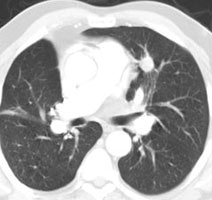

True negative PET scan: The patient in the scan below had a 1.5 cm left upper lobe nodule (shown below) that could be retrospectively identified on a prior CT scan at which time it measured only 4 mm. A PET scan was performed (below right), but demonstrated no uptake in the lesion (some cardiac activity can be seen more anteriorly). Because the nodule had enlarged from a prior exam, the nodule was resected and found to be a granuloma. Nodules larger than 1.5 cm that are negative on PET scans have a highly likelihood for representing benign or indolent lesions. |